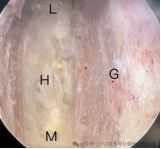

4.微创脊柱内镜技术:PELD+UBE+OSE

脊柱内镜技术是一项开展较早的脊柱外科微创技术,与传统开放手术相比,它是借助天然解剖间隙建立微创工作通道,解除神经压迫;对椎旁肌肉损伤较小,且能够最大程度地保留完整的脊柱结构,维持了术后脊柱的稳定,具有创伤小、出血少、恢复快、并发症少、疗效确切等优点。目前已开展椎间孔镜下髓核摘除术,单侧双通道脊柱内镜(UBE)下椎管减压术并处于区域内领先水平。我院在江苏省内率先开展了单孔分体式脊柱内镜技术(OSE),处国内领先水平。

单孔孔镜

单侧双通道技术

单孔分体式内镜下腰椎固定融合技术